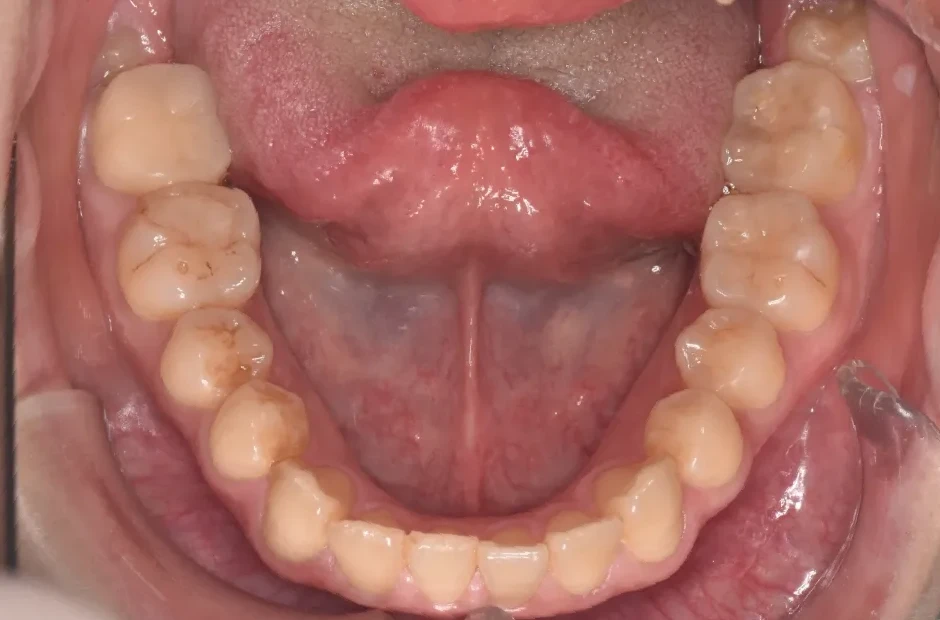

叢生

| 診断名・主訴 | 叢生 |

|---|---|

| 年齢・性別 | 43歳・女性 |

| 治療期間・回数 | 2年7か月 27回 |

| 治療に用いた主な装置 | 舌側矯正 |

| 抜歯部位 | 両顎4,4 |

| 治療費 | 100万円(税抜) |

| リスク・副作用 | 装置による違和感・疼痛・歯肉退縮・歯根吸収・虫歯のリスクなど |

治療前

治療中

治療後